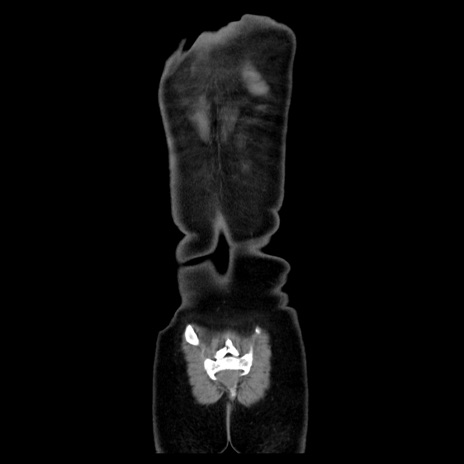

MRI(4日後)